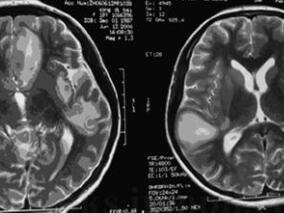

1小时条评论52岁女性,受到惊吓后发生认知障碍且进展迅速。多次检查头颅MRI,显示大脑半球多发性病灶。磁共振波谱分析(MRS)检查显示胆碱(Ch)波峰增高,可见乳酸(La)波峰。提示病灶部位新陈代谢增快,同时伴有组织缺氧表现,提示肿瘤?线粒体脑病?最终左侧开颅颞叶病变活...